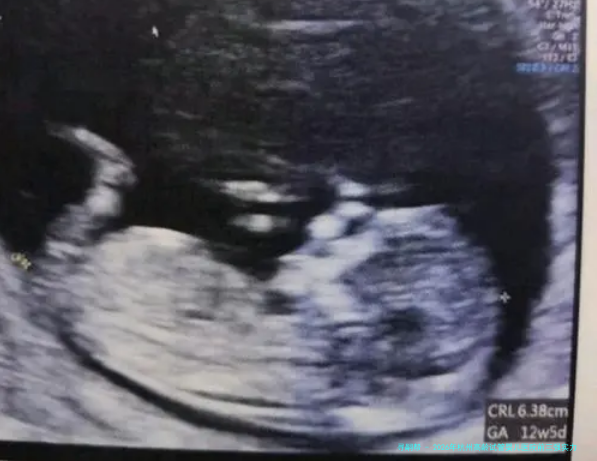

患者真实评价:“我系四十四岁在这里做的三代试管,1次成功。感觉这里的实验室技术真的很强,医生给方案也很果断,没让我走弯路。即是人过多了,排队有些艰苦。”

病患实际评估:“我43岁,在邵逸夫做了两次。次没成,医生很耐心地帮我解析了原因,调整了方案。第二次移植前还专门进行了宫腔灌注。整个团队给人的印象很专业、很温馨,不是冷冰冰的流水作业线操作。”

病患现实评估:“我系朋友推荐来的,42岁。这里舒静医生尤其仔细,给我定的方案取卵子数未几,但配成的胚胎质量不错。1次移植就怀上了,现如今宝宝很健康。费用印象也相比透明。”